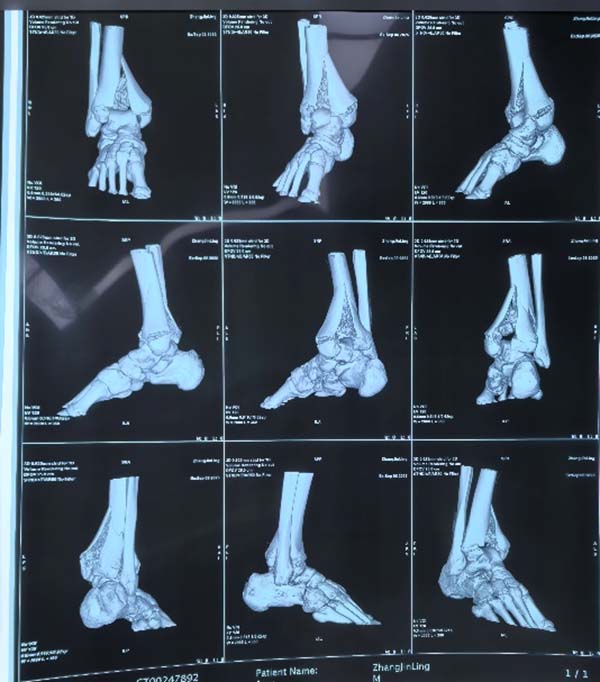

该款机器人适用于关节内骨折的撬拨复位及穿针定位,能够有效帮助医生对关节内复杂的骨折进行毫米级的定位、复位、固定操作。并能够结合前提课题完成的骨折AI识别规划软件,对骨折块进行撬拨复位。目前已在南阳市中医院开展临床研究三十余例。

两款联合使用复位复杂的Pilon骨折: